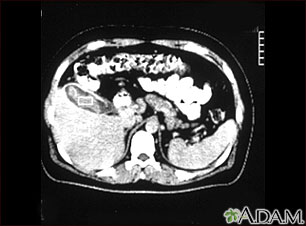

This is a CT scan of the upper abdomen showing cholecystitis (gall stones).